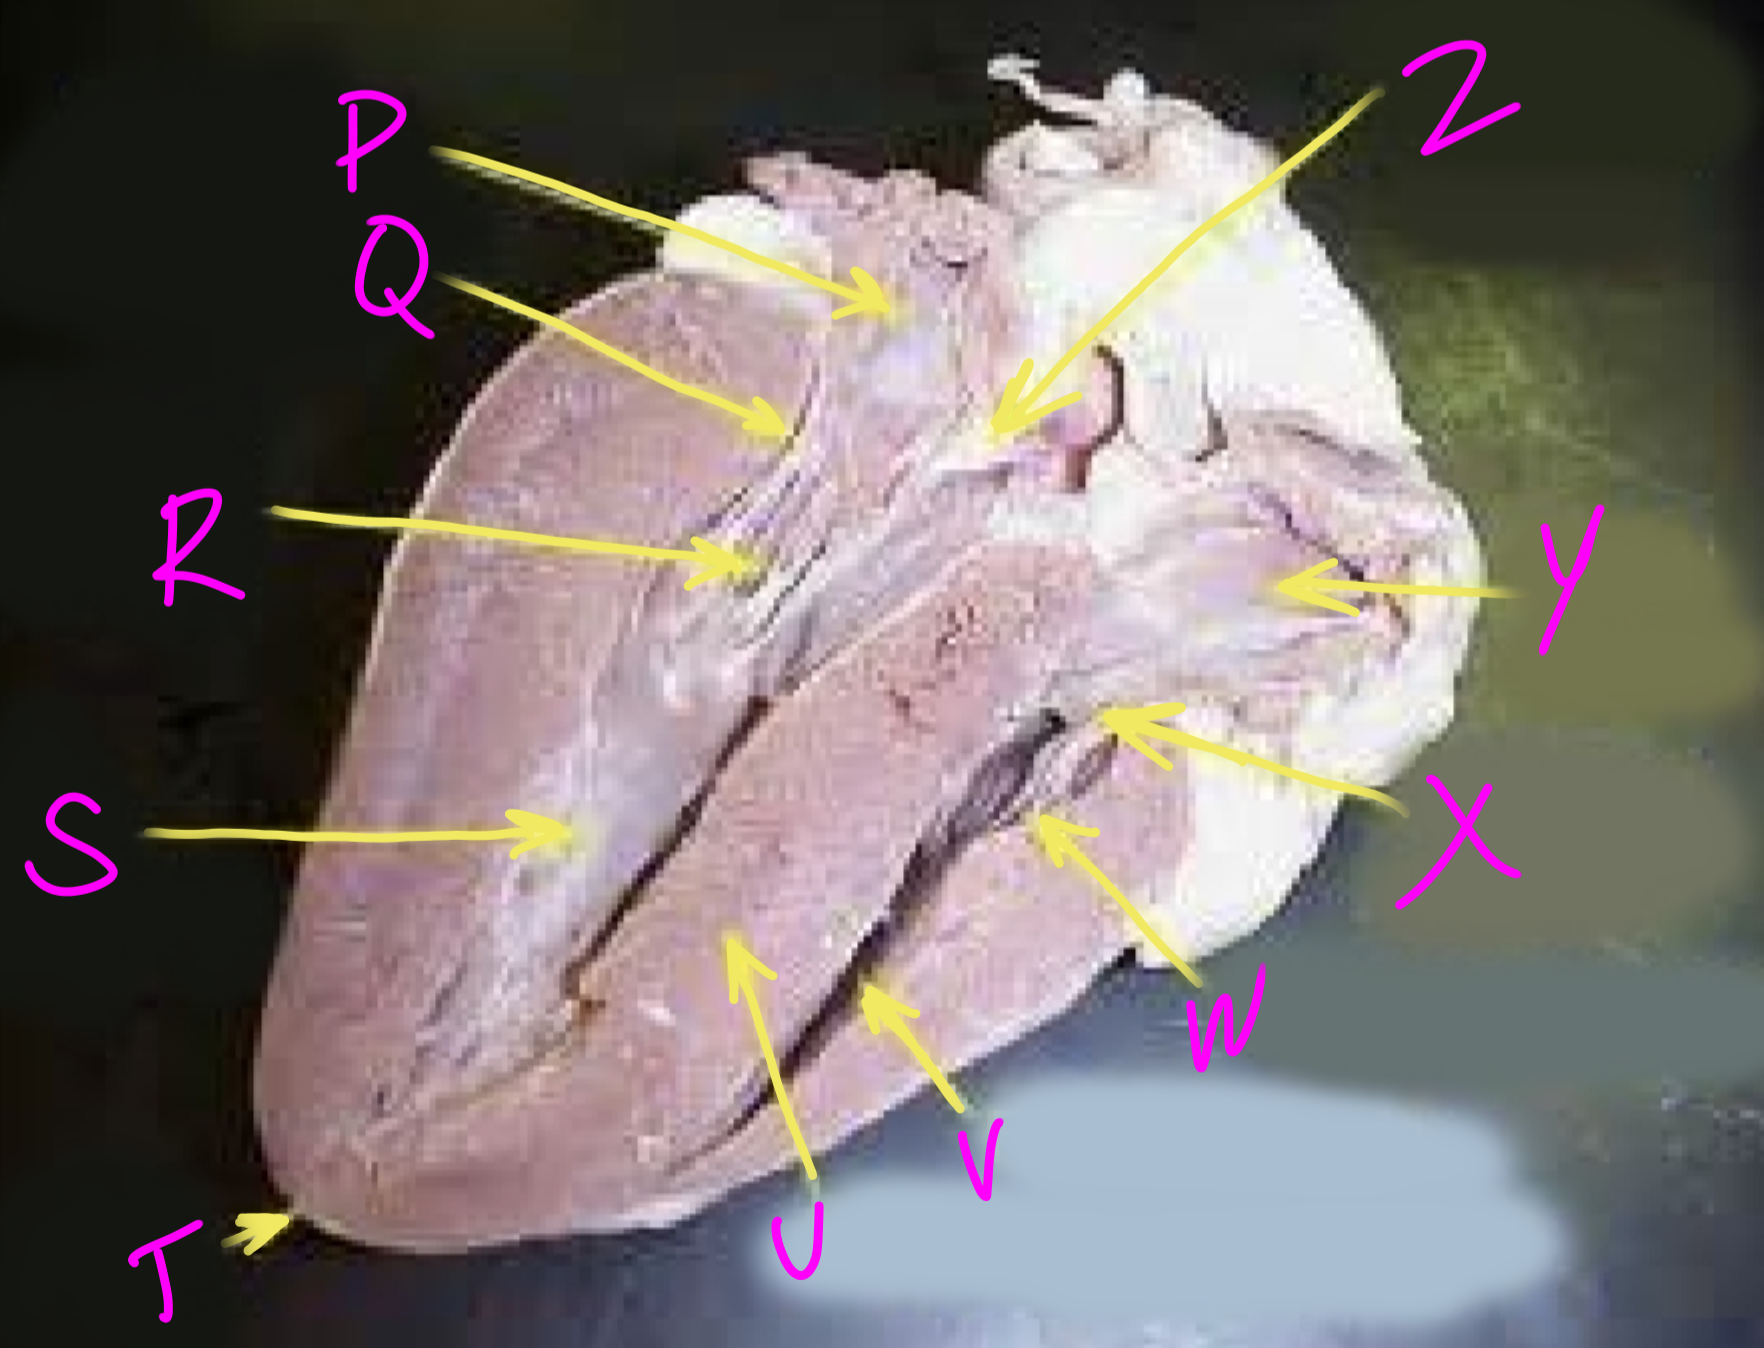

P

Left atrium

Q

Bicuspid valve - allows blood to flow from the left ventricle to the aorta

R

Right chordae tendinae - hold AV valves in place

S

Left ventricle

T

Apex - pumps blood out of the ventricles

U

Interventricular septum - divides the right and left ventricles

V

Right ventricle

W

Left chordae tendinae - hold AV valves in place

X

Tricuspid valve

Y

Right atrium

Z

Aortic semilunar valve - prevent backflow